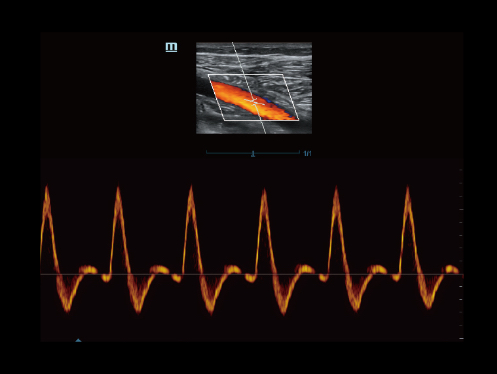

-Smart Track

It's Mindray unique feature to reduce repetitive, time-consuming scanning steps in vascular exams. Smart Track provides intelligent and real-time vessel tracking and real-time image optimization of Color and PW.